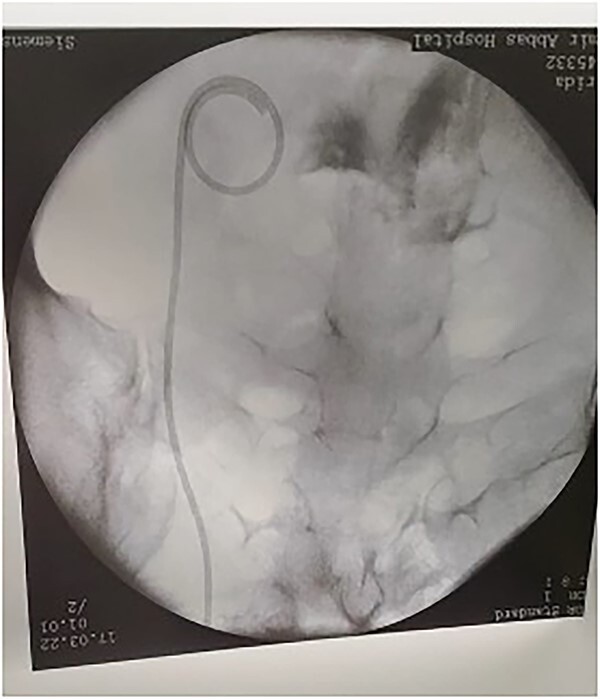

Guide wire passed through the UV fistula.

Figure 6.

After insertion of DJ stent.

The patient tolerated the procedure very well and was transferred to the recovery room in stable condition. We did inform the patient that there is a small likelihood of developing a fistula within 2 weeks post-operatively. The patient did well in the post-operative period, recovered and was discharged to home in a stable condition. Unfortunately, on day 8, post-operatively, she started to have a leakage of urine per vagina. She was admitted for investigation, a CT Urogram was done with delayed images that confirmed the diagnosis of ureterovaginal fistula. The urologist was involved and consulted at this point; the plan was to take the patient for cystoscopy with retrograde ureteroscopy. Ureteroscopy wth retrograde fluoroscopy showed evidence of a ureterovaginal fistula (Figs 4 and 5) in which a DJ stent was inserted successfully (Fig. 6). The patient was explained about the post-operative course and plan. We decided to keep the stent for 12 weeks and then re-assess. The patient was covered by prophylaxis low-dose nitrofurantoin single daily dose of 100 mg. Fortunately, the leakage decreased gradually until it stopped. The patient was taken to the operating room to re-assess the fistula by cystoscopy and retrograde fluoroscopy. Retrograde fluoroscopy confirmed that the fistula healed. The stent was removed, and the patient was discharged to home in a stable condition.